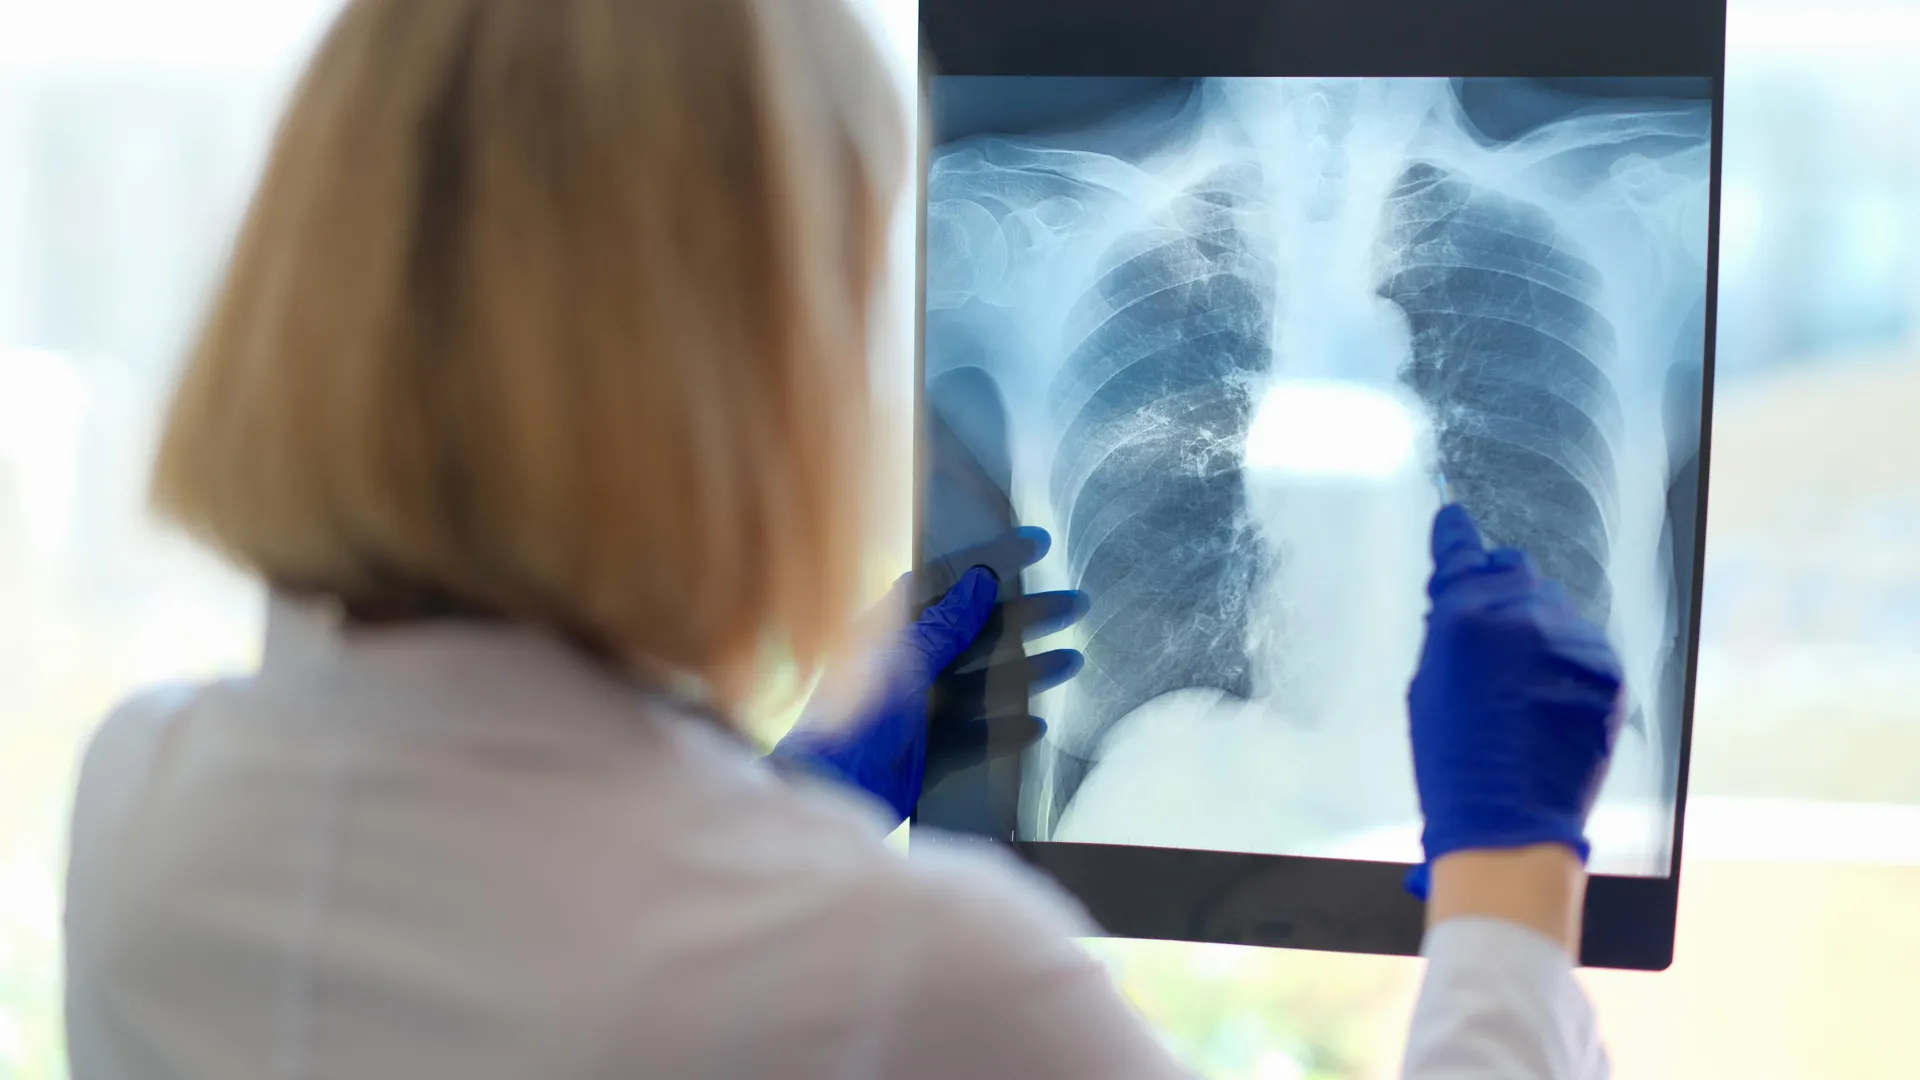

The study included 57 people diagnosed with chronic fatigue syndrome and 25 healthy individuals of similar age and activity level. All participants completed two days of cardiopulmonary exercise tests. During these sessions, the researchers monitored heart rate, blood pressure, oxygen uptake efficiency, blood oxygen saturation, and how much effort participants used to breathe. They also analyzed breathing rate and patterns to detect signs of hyperventilation and dysfunctional breathing.

Results showed that people with chronic fatigue syndrome took in roughly the same amount of oxygen as the control group — their peak VO2 max was similar. However, 71% of the chronic fatigue group showed breathing abnormalities, such as hyperventilation, dysfunctional breathing, or both.

Almost half of the chronic fatigue participants breathed irregularly during the tests, compared to only four people in the control group. About one-third of the fatigue patients hyperventilated, while just one person in the control group did. Nine patients had both hyperventilation and dysfunctional breathing, a combination not seen in any of the controls.